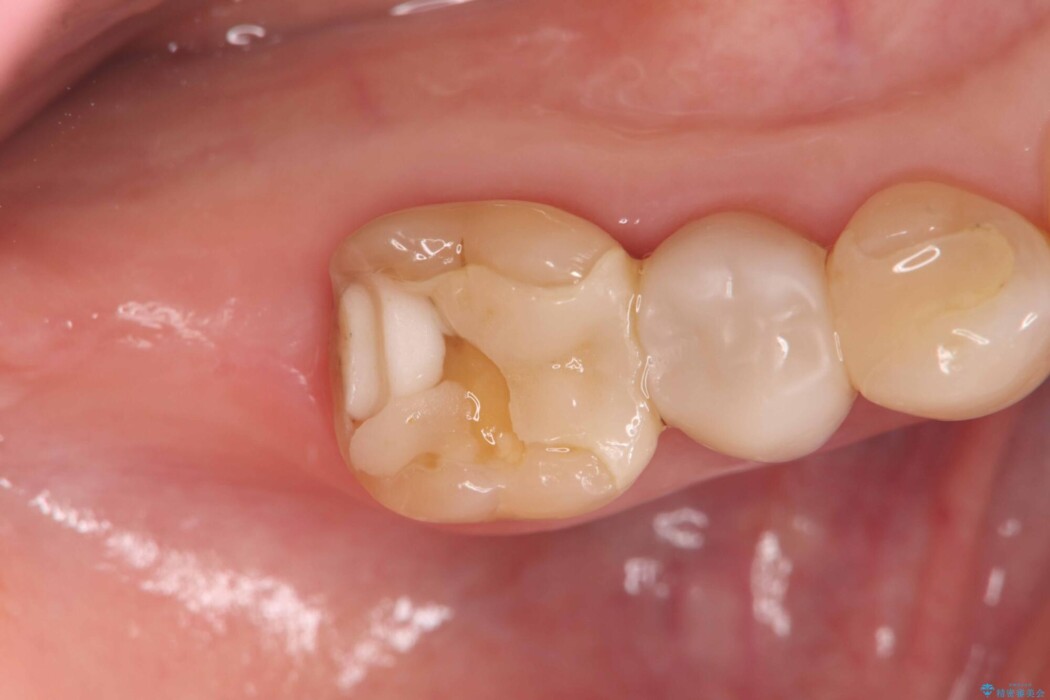

他院で装着されたセラミックインレー(MOD窩洞)が破折したとご来院されました。

MOD窩洞のように欠損範囲が大きい場合、インレーでは咬合力に対する耐久性が不足し、破折リスクが高くなるケースがあります。

歯の中央から両側にかけて大きく削られている(MOD窩洞)状態でした。

噛む力がかかることで、インレーでは負担に耐えきれず破折してしまったと考えられます。